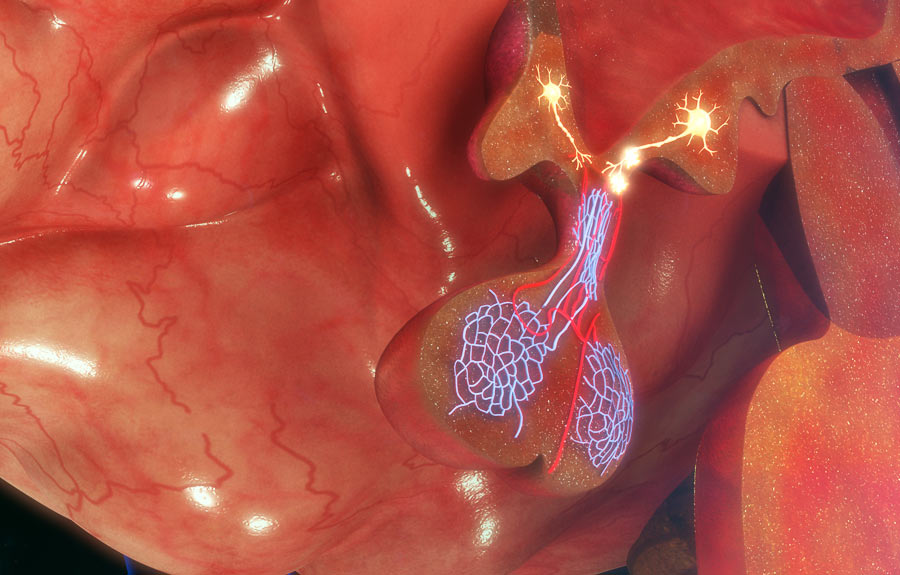

A acromegalia é uma doença rara que ocorre devido à produção excessiva do hormônio do crescimento (GH) no corpo após o término do período de crescimento. Essa produção em excesso é geralmente causada por um tumor benigno na glândula hipófise, chamado adenoma hipofisário.

O tratamento da acromegalia tem como objetivo normalizar os níveis hormonais, aliviar os sintomas e prevenir complicações. Em geral, a cirurgia para ressecção do tumor hipofisário é a principal opção terapêutica, sendo a via endoscópica endonasal a principal escolha na maioria dos pacientes. Em alguns casos, podem ser utilizados medicamentos para reduzir a produção de hormônio do crescimento ou bloquear seus efeitos.